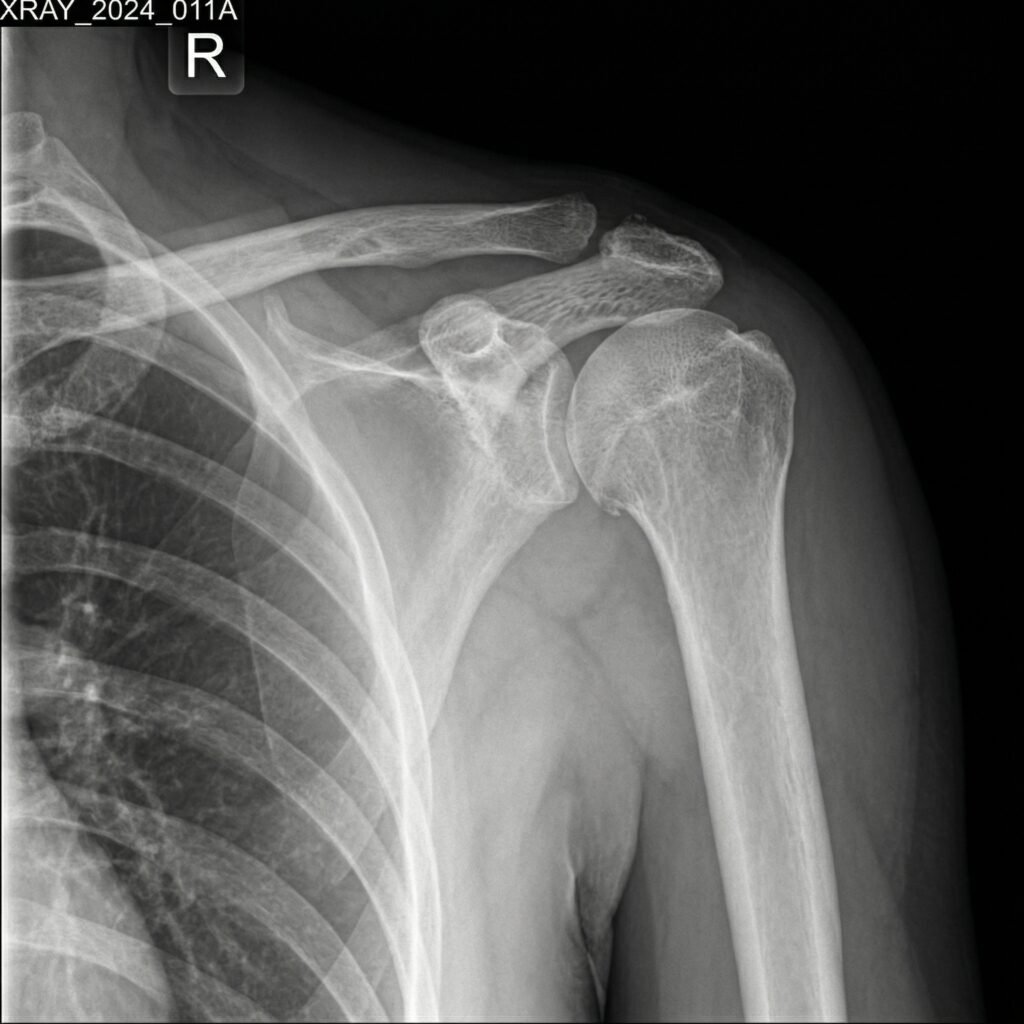

Shoulder injuries can result from trauma, sports activities, or repetitive strain, leading to pain, weakness, and limited movement. Common conditions include rotator cuff tears, shoulder instability, frozen shoulder, and ligament injuries that can significantly impact daily activities.

Shoulder arthroscopy is a minimally invasive surgical procedure used to diagnose and treat various shoulder joint conditions with high precision. It is commonly recommended for problems such as rotator cuff tears, shoulder instability, labral injuries, and cartilage damage that cause pain and restrict movement.

Shoulder replacement surgery is an advanced orthopedic procedure performed to relieve chronic shoulder pain and restore joint function in patients suffering from arthritis, severe fractures, or joint degeneration. When non-surgical treatments fail to provide relief, this procedure offers a long-term solution for improved mobility and quality of life.